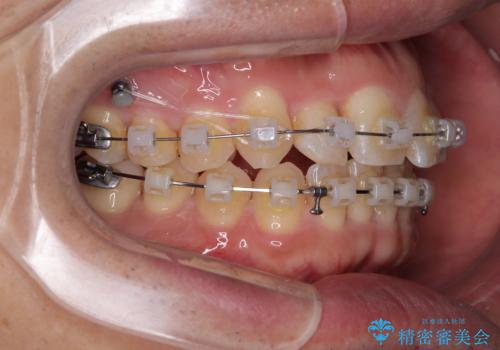

- クリアブラケット

- 1年1ヶ月

- 上下前歯のデコボコを気にして来院された患者様です。

ワイヤー矯正でもマウスピース矯正でも可能でしたが、短期間で、自身の手を煩わせることなく治療を行いたいとのことで、ワイヤー装置にて矯正治療を行うこととしました。

上顎前歯の舌側転位が顕著であったため、治療期間が長くなると思われましたが、僅か1年で無事に終えることができました。